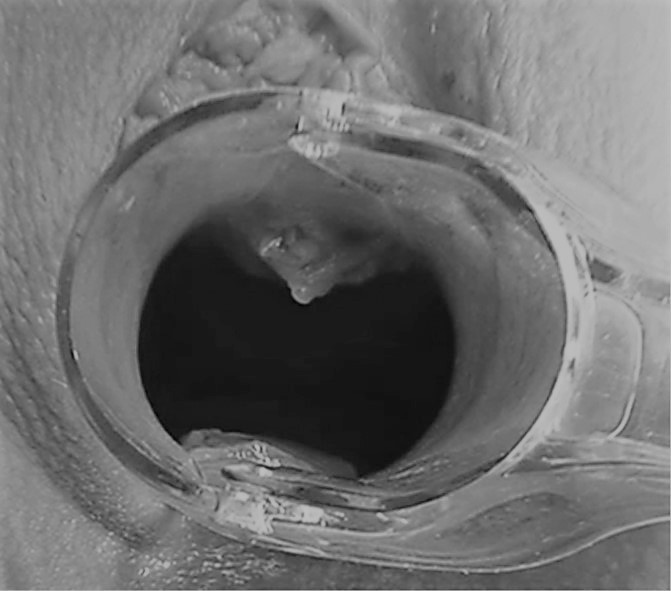

Ход операции

Врач вводит гиалуроновую кислоту непосредственно в точку G, которую предварительно определяет при пальпации, тем самым увеличивая ее упругость и амортизацию.